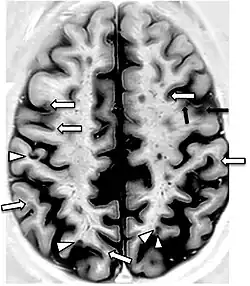

A 2019 literature review identified hypertension and history of pre-eclampsia as significant risk factors for the accelerated decline of cognitive function in women during midlife. Although the mechanism remains unclear, neuroimaging studies included in the review found that those with hypertension have evident structural changes in their brains; specifically, gray matter brain volume decreased and white matter hyperintensity volume increased.[18]